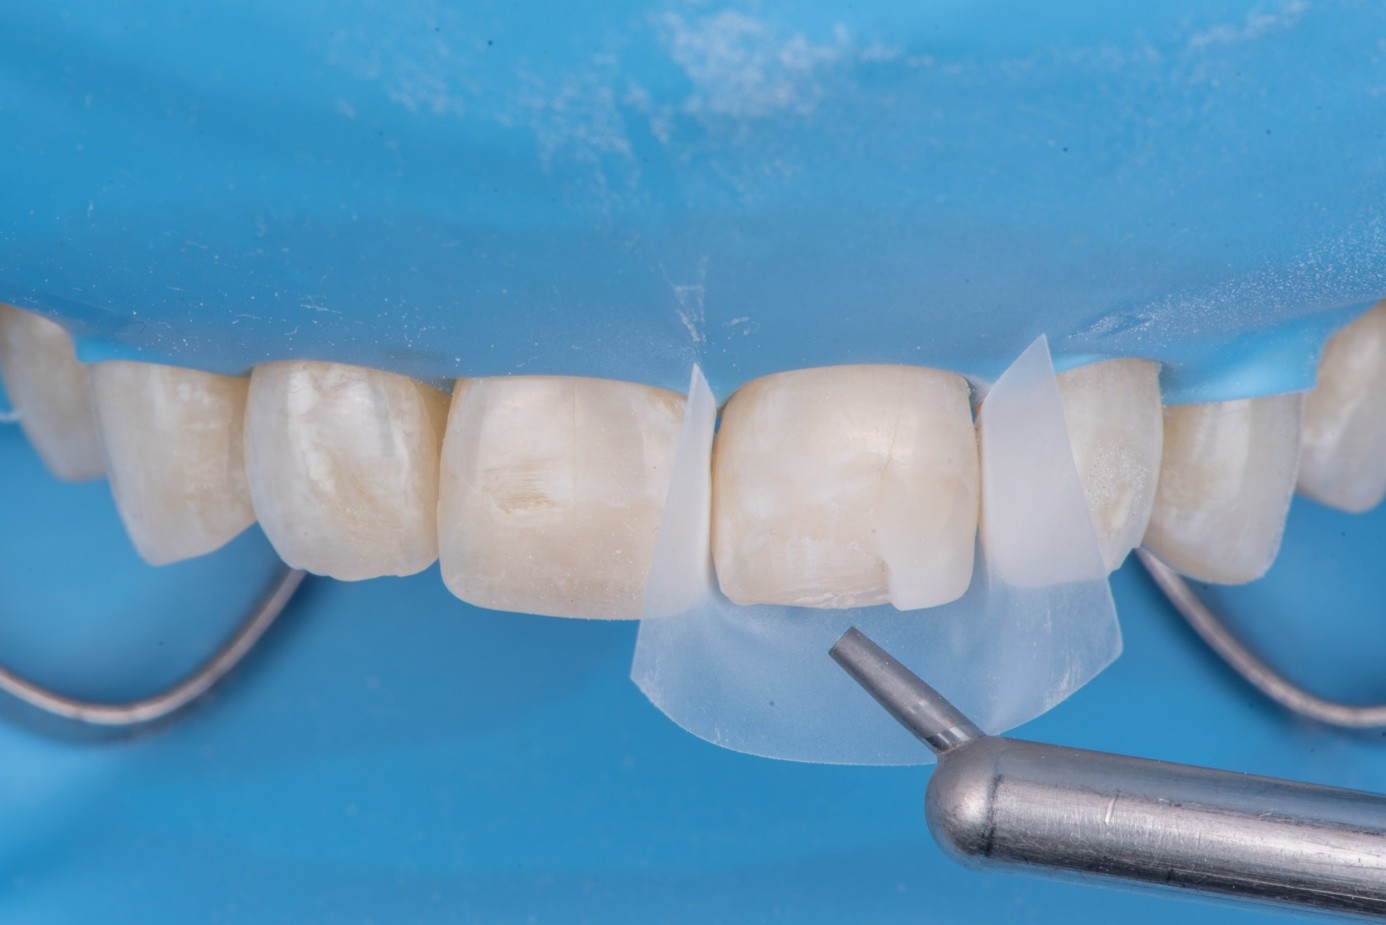

(25.) Correction and removal of composite excess, followed by light polymerization.

Figure 25

(26.) Correction and removal of composite excess, followed by light polymerization.

Figure 26

Before light-curing, flowable composite resin was placed in the cavity, and the fractured segment was repositioned precisely into its original location. Heated packable composite was avoided due to thinness and brittleness of the fractured piece. Excess bonding and composite were carefully removed using a microbrush. The restoration was then polymerized from multiple directions to ensure optimal cure (Figure 25 and Figure 26). Finally, the restoration was polished and contoured to blend seamlessly with the surrounding tooth structure and adjacent composite (Figure 27).